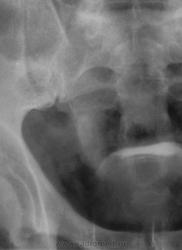

Вопрос в другом-а в мочеточнике ли это? А конкрементом дивертикула пузыря не может быть, тут УЗИстам поработать надо, при работающей рентгеноскопии можно провести цистографию, повернуть пациента, посмотреть-где же эта тень. А операций на сосудах не было?

Я не про "утверждаю", Боже спаси, для мочеточника тень очень больших размеров, хотя расположена вдоль его проекционной оси, но здесь же проекция крупных сосудов, стенты сейчас могут быть всякими разными, а потом-в малом тазу не только у женщин, но и мужчин хватает всякого, что может обызвествляться. А верхняя тень-типично для желчного пузыря.

Признавайтесь, куда делась средняя треть правого мочеточника? Ее как-будто ножом отрезали под линейку, а ниже-сплошное безобразие! "ЧТО" может как обезобразить орган-банальная МКБ с частичной обтурацией просвета или опухоль? А в пузыре тоже камни?

А деформация мочевого пузыря никого не смущает?

Отчего же не смущает?))) смущает...она и есть первопричиной образования ТАКОГО камня в мочеточнике, теперь об этом можно сказать с уверенностью, ее генез - выраженое увеличение размеров простаты.

Мне кажется, что тень в проекции н/3 правого мочеточника не меняет своей интенсивности на ОМПС и экскреторных урограммах. Отсроченный снимок просится и рентгенография малого таза в косых проекциях. Возможно, это НЕЧТО сдавливает н/3 правого мочеточника извне.

С простатой при отсутствии УЗИ достаточно пальцевого осмотра хирургом до экскреторного исследования. Если простата не увеличена пальпаторно, то получив такую картинку мочевого пузыря на первых минутах после введения контраста, я бы сделал косые снимки мочевого пузыря (заодно и тень в н/3 правого мочеточника покрутить).